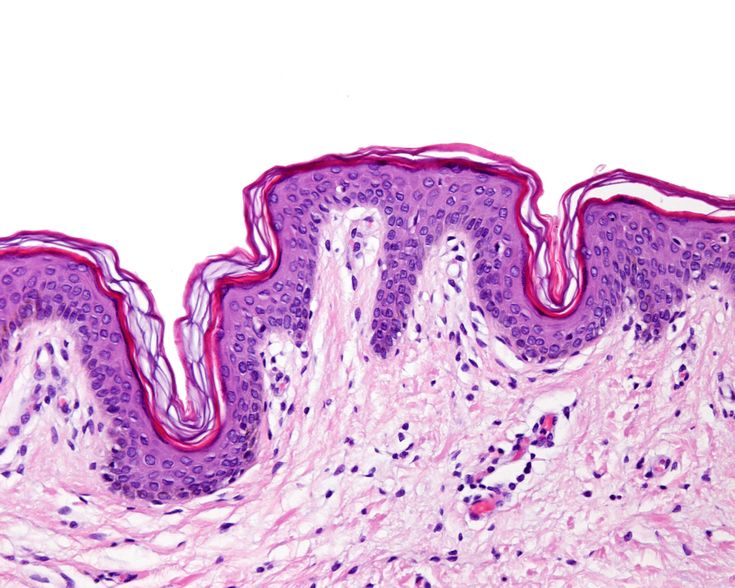

CCS.0616 - HISTOLOGIA